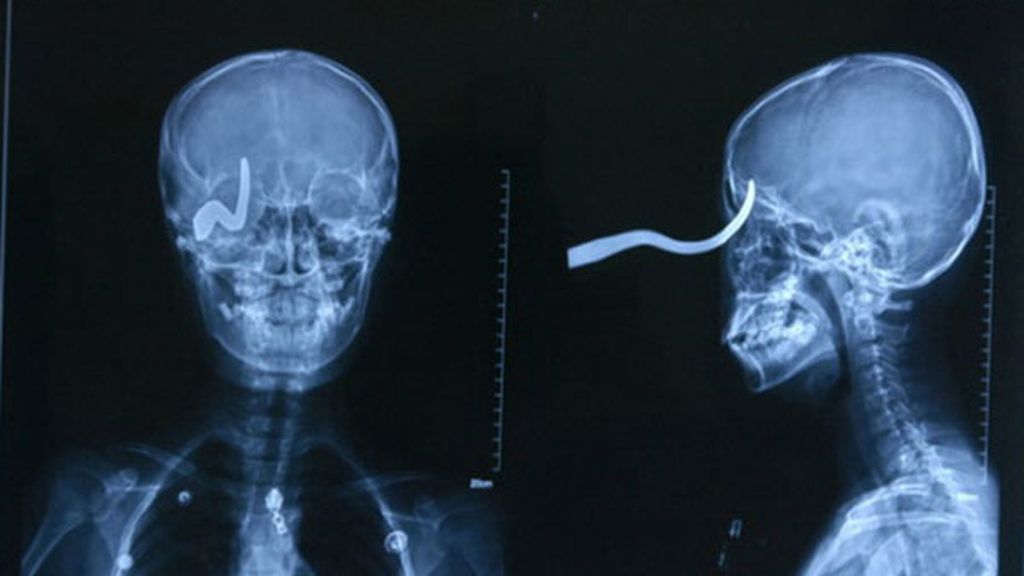

Xiaolin Niu ha perdido un ojo al clavarse un gancho. Estaba jugando en el colegio y se cayó sobre una barra de acero, que lamentablemente se incrustó en su ojo. A pesar de lo terrible del accidente ha tenido suerte. El gancho le atravesó el cráneo y se quedó a dos milímetros del cerebro. "Podría haber muerto", ha asegurado el cirujano que le atendió.